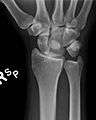

Dislocated lunate

Dislocated lunate- Wrist joint. Deep dissection. Posterior view.